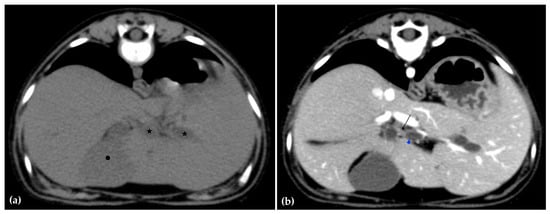

Abdominal radiographs showed no significant abnormalities except a large amount of fecal material in the large intestine. The patient was placed in dorsal recumbency for an abdominal ultrasound (microconvex and linear probes 12–18 MHz, Epiq 5G, Philips Ultrasound, Bothell, WA, USA), with the ventrum shaved from above the xiphoid to the pubis in a roughly square-shaped region. Ultrasound coupling gel and alcohol were used for image optimization. The gallbladder was moderately filled with anechoic fluid and the cystic duct appropriately tapered to the common bile duct (CBD). The CBD could not be traced in its entirety, but the more distal identified segments were multifocally dilated, measuring up to 0.6 cm in diameter (outer wall to outer wall; Figure 1a). At its distal-most aspect, as it approached the duodenal papilla, the CBD abruptly tapered without a discrete intraluminal or extraluminal cause (Figure 1b). Several intrahepatic biliary ducts within the left liver hemisphere were distended distally, measuring up to 0.5 cm in dilation (inner wall to inner wall; Figure 2a,b). No intrahepatic biliary duct dilation of the right hepatic hemisphere was noted. Due to a concern for an unidentified biliary duct obstruction contributing to the patient’s clinical signs/changes, a dual phase contrast abdominal computed tomographic (CT) study was pursued for further evaluation.

Figure 1.

Ultrasound images of the liver. A portion of the common bile duct (CBD) is moderately-markedly distended (between + calipers) (a). Ultrasound image of the duodenum (black-rimmed white star), common bile duct (white arrowhead), and pancreas (blue-rimmed white circle). The distal common bile duct at the level of the duodenal papilla with abrupt narrowing (between calipers) (b).